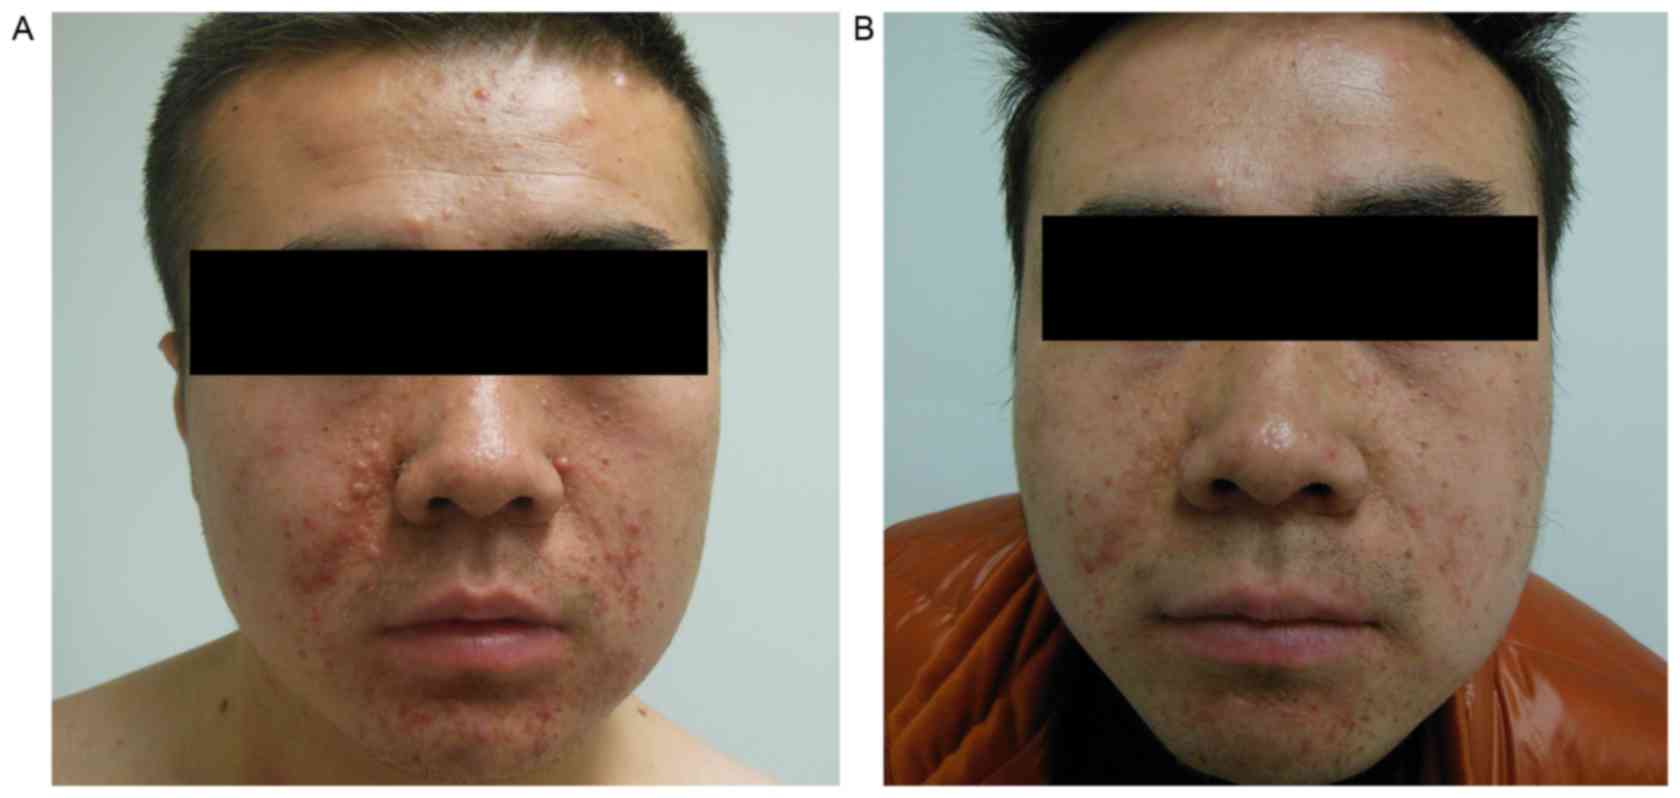

baseline data (Fig. 3). Changes to

the facial angiofibromas in 1 patient are shown in Fig. 4, from which it can be observed that

the angiofibromas had become much flatter, smaller and lighter in

color compared with those prior to therapy.

study, following treatment with everolimus for 3 months, the

maximum diameter of TSC-RAML in the 2 patients decreased by 4.90

and 5.30 cm, respectively, the intermittent abdominal pain

disappeared completely and the facial angiofibromas improved.